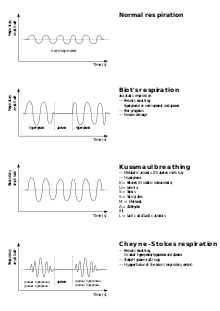

| Breathing patterns | |

| |

| Graph showing normal as well as different kinds of pathological breathing patterns. |

Abnormal breathing patterns include Kussmaul breathing, Biot's respiration and Cheyne–Stokes respiration.

Other breathing disorders include shortness of breath (dyspnea), stridor, apnea, sleep apnea (most commonly obstructive sleep apnea), mouth breathing, and snoring. Many conditions are associated with obstructed airways. Chronic mouth breathing may be associated with illness.[28][29] Hypopnea refers to overly shallow breathing; hyperpnea refers to fast and deep breathing brought on by a demand for more oxygen, as for example by exercise. The terms hypoventilation and hyperventilation also refer to shallow breathing and fast and deep breathing respectively, but under inappropriate circumstances or disease. However, this distinction (between, for instance, hyperpnea and hyperventilation) is not always adhered to, so that these terms are frequently used interchangeably.[30]